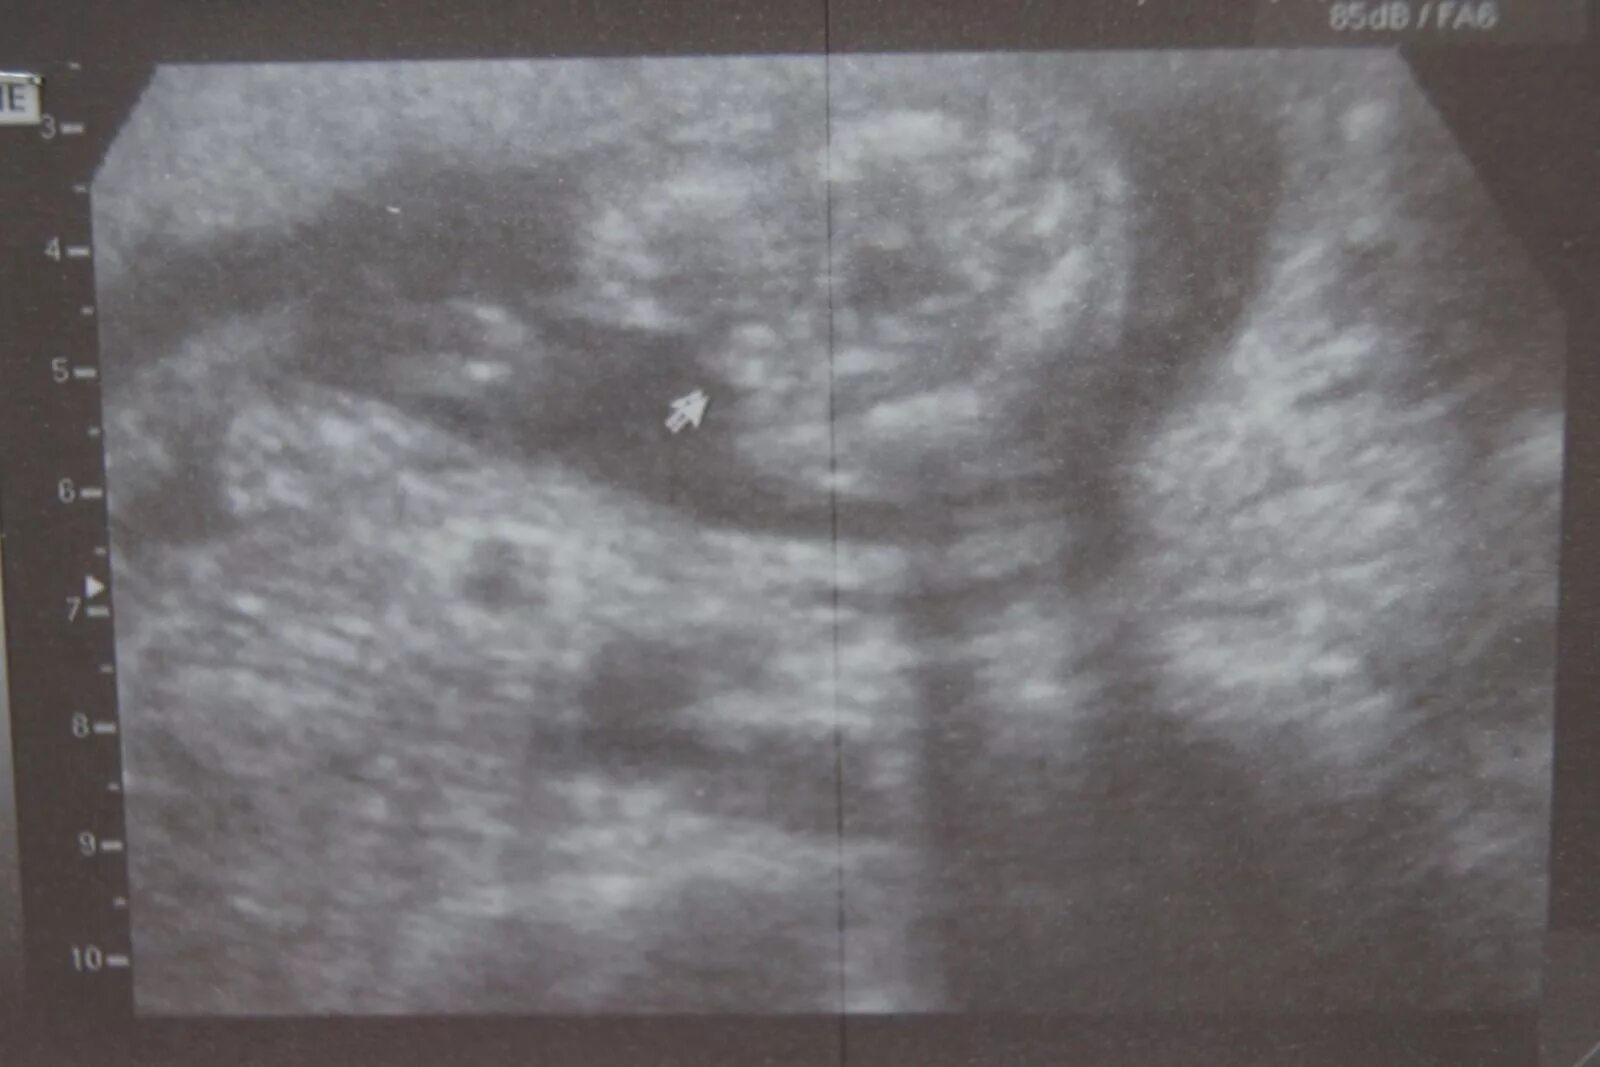

Узи 17 недель девочка